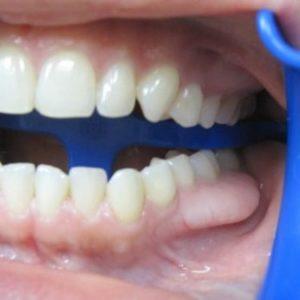

Экзостоз в стоматологии представляет собой наросты (остеофиты), которые возникают в результате разрастания костной или хрящевой ткани.

Эти образования проявляются в виде выступов на поверхности неба или нижней челюсти.

Внешний вид остеофитов напоминает шиповатые уплотнения слизистой оболочки, окрашенные в розовые или белые оттенки.

Размеры таких наростов могут варьироваться от небольших, размером с горошину, до крупных, достигающих величины яблока. Обычно они располагаются рядом с молярами, как на стороне неба, так и на изгибе нижней челюсти.